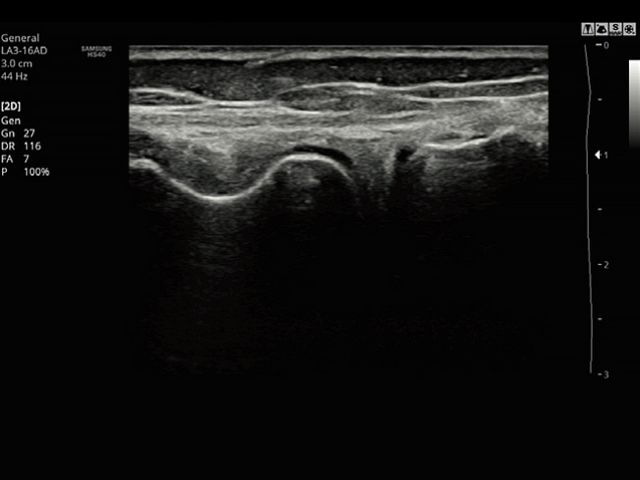

Panoramic imaging displays as an extended field-of-view so users can examine wide areas that do not fit into one image as a single image. Panoramic imaging also supports angular scanning from linear transducer data acquisition.

LA3-16ADApplication:Small parts, Vascular, Musculoskeletal, Abdomen, Obstetrics, Gynecology, Pediatric, Emergency |